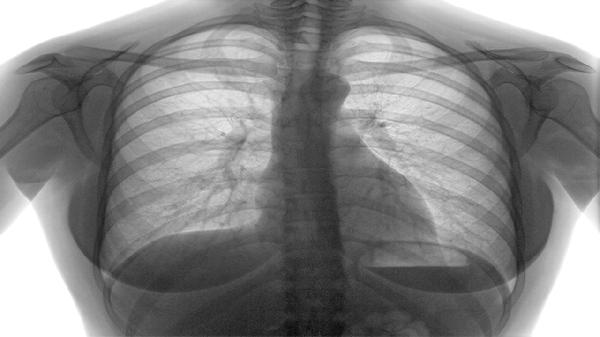

清肺化痰丸主要用于治疗肺热咳嗽、痰多黏稠、胸闷气促等呼吸道症状,适用于由风热犯肺或痰热壅肺引起的病症。主要有清肺化痰、止咳平喘、清热宣肺、利咽消肿、缓解支气管痉挛等功效。

方中苦杏仁、紫苏子具有舒张支气管作用,能缓解咳嗽气喘症状,尤其适用于哮喘或慢性阻塞性肺疾病急性发作时的辅助治疗。若出现喘息伴哮鸣音,需联用布地奈德福莫特罗粉吸入剂等药物。服药期间需监测心率变化。

对于支气管哮喘或过敏性咳嗽导致的支气管平滑肌痉挛,该药能通过抗炎作用减轻气道高反应性。严重发作时应及时使用硫酸沙丁胺醇吸入气雾剂,并就医调整治疗方案。用药期间需远离烟雾等刺激物。